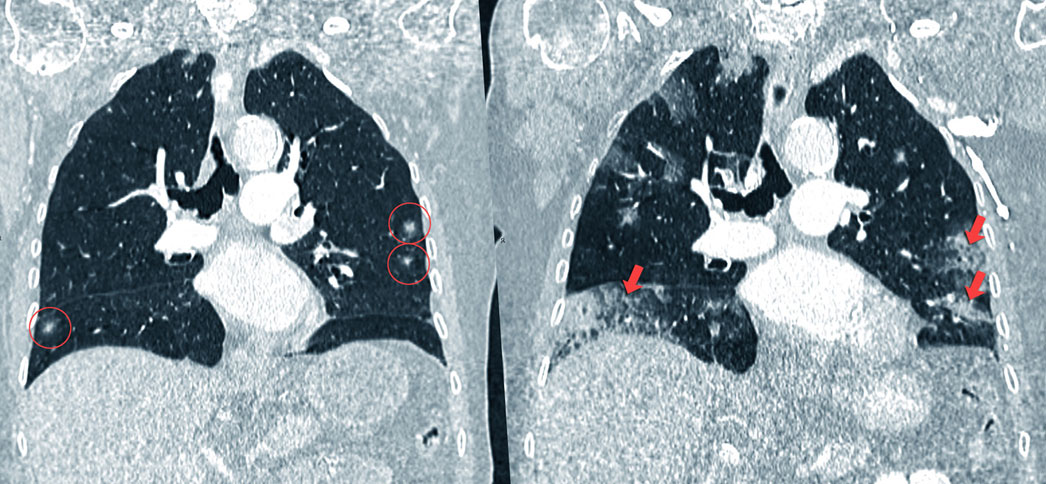

Evolución durante seis meses de un cáncer de pulmón

"El cáncer puede ser detectado en estadios más precoces con el uso de la tomografía computarizada de baja radiación. Esta prueba permite identificar el tumor en una fase anterior, cuando forma pequeños nódulos en el pulmón y antes de que se extienda a otras zonas del organismos. Esta tecnología ha aumentado la tasa de curaciones", detalla el doctor José María Echave-Sustaeta

"En la actualidad solo un 15% de los carcinomas no microcíticos de pulmón permite una intervención curativa; mientras que en los programas de cribado mediante tomografía computarizada se ha conseguido la detección de entre un 65 y un 85% de tumores en estadios precoces", continúa el doctor Echave-Sustaeta, quien cree que las personas que están en el grupo de alto riesgo deberían hacerse la prueba una vez al año.